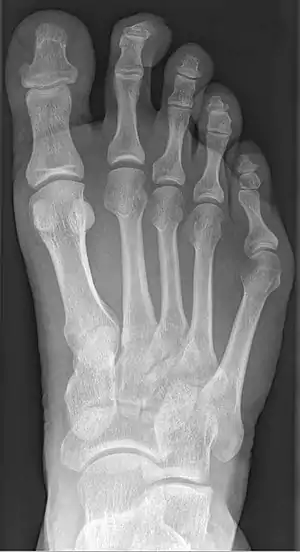

| Radiograph showing a tailor's bunion | |

Tailor's bunion is easily diagnosed because the protrusion is visually apparent. X-rays may be ordered to help the surgeon find out the severity of the deformity.